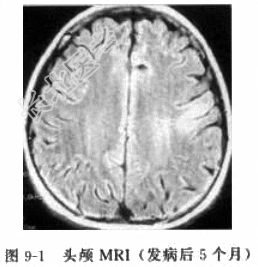

患者女性,14岁,右利手。因“发作性右侧肢体抽搐22个月,右侧肢体无力16个月”入院。患者于22个月前无明显诱因出现发作性头右偏,不能言语,持续约1min,当时无意识障碍。于当地医院检查行头颅CT及MRI检查颅内未见明显异常,脑电图提示边缘状态脑电图。患者2天后出现右口角持续性抽搐,于北京某医院就诊,诊断癫痫,予“卡马西平(得理多)”口服治疗后好转。18个月前出现右上肢持续性抽搐,再次前往北京某医院就诊,MRI印象左侧额叶病变,首先考虑炎症性病变,脑电图为高度不正常儿童脑电图,左侧半球为著。17个月前右上肢转为间断性抽搐,并逐步出现右下肢持续性抖动,卧位时明显。并逐步出现右侧面肌无力、上肢无力以手部为甚,而后出现下肢无力,呈进行性加重。1个月前再次于北京某医院诊断考虑线粒体脑肌病可能,予肌肉活检后排除该病。目前此类症状发作频繁,发作形式表现为:头右偏,右口角及上下肢抽搐,发作时意识清楚,言语稍欠流利,抽搐时间短则数十秒,长则2min,发作约每日二十余次。药物治疗方面:由单一应用得理多到逐渐联合应用托吡酯(妥秦)、拉莫二嗪等多种抗癫痫药物联合应用。现口服得理多、妥泰和拉莫三嗪,仍不能满意控制癫痫发作。患者发病前3个月上呼吸道感染(感冒)发热,最高体温为39℃,发热持续4天后好转。患者发病以来,智力逐渐下降,较同龄儿童明显下降。体格检查T37.0℃,R19次/min,P80次/min,BP120/60mmHg。专科查体:神志清楚,言语欠流利,右侧鼻唇沟,浅口角左侧歪斜,伸舌稍右偏,耸肩右侧稍力弱。右手屈曲挛缩,右下肢内翻畸形,右上肢近端肌力4级,远端3级,右下肢肌力4+级,左侧肢体肌力5级,左侧腱反射正常存在,右侧肱二头肌、肱三头肌、膝腱反射及跟腱反射亢进,右侧Babinski征、Cordon征、Chaddoch征、Hoffman征阳性。辅助检查头颅MRI检查(发病后5个月)(图9-1):左侧额叶沿中央沟两侧脑灰质可见长T1长T2信号、Flair高信号,局部脑组织略肿胀,脑沟略浅。头颅MRI(发病后9个月)(图9-2):左颞叶皮质及皮质下多发片状长Tl长T2信号、Flair高信号,与发病后5个月比较左额叶病变范围扩大,左颞叶为新出现病变。头颅MRI(发病后19个月)(图9-3):与发病后9个月相比,①左额颞进展性病灶,白质逐步受累,左内侧颞叶、扣带回额内侧回、旁中央小叶逐渐受累;②左侧半球进行性脑萎缩,以额颞叶为主。